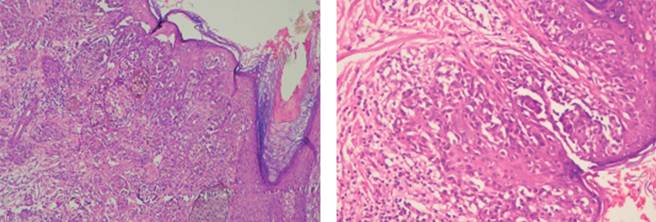

Se decide manejo integral por medio del departamento de hematología; se realiza biopsia de hueso y aspirado de médula ósea (AMO: médula ósea con hiperplasia de la serie eritroide y fibrosis reticulínica grado 3) (Figura 4) y se hacen varias transfusiones (4 paquetes globulares durante su estancia hospitalaria) por parte del Servicio de Neumología; se efectúa broncoscopia con toma de biopsias de masa localizada en bronquio de lóbulo apical posterior de pulmón derecho con resultado de patología final de adenocarcinoma pulmonar y del Servicio de Urología, realizando ureteroscopia y colocación de catéteres doble J, sin especificar la causa de la obstrucción ureteral. Debido al manejo integral que se proporciona, el paciente se mantiene estable durante su estancia intrahospitalaria.

El aspirado de médula ósea es difícil de realizar dadas las características fibróticas; los principales hallazgos son hiperplasia megacariocítica y neutrofílica; sin embargo, no son diagnósticos. La biopsia de médula ósea es necesaria para demostrar la fibrosis, asociada a hiperplasia megacariocítica y osteoesclerosis. Se debe realizar en forma rutinaria la búsqueda de mutaciones genéticas, principalmente JAK2, BCR-ABL, MPL.2